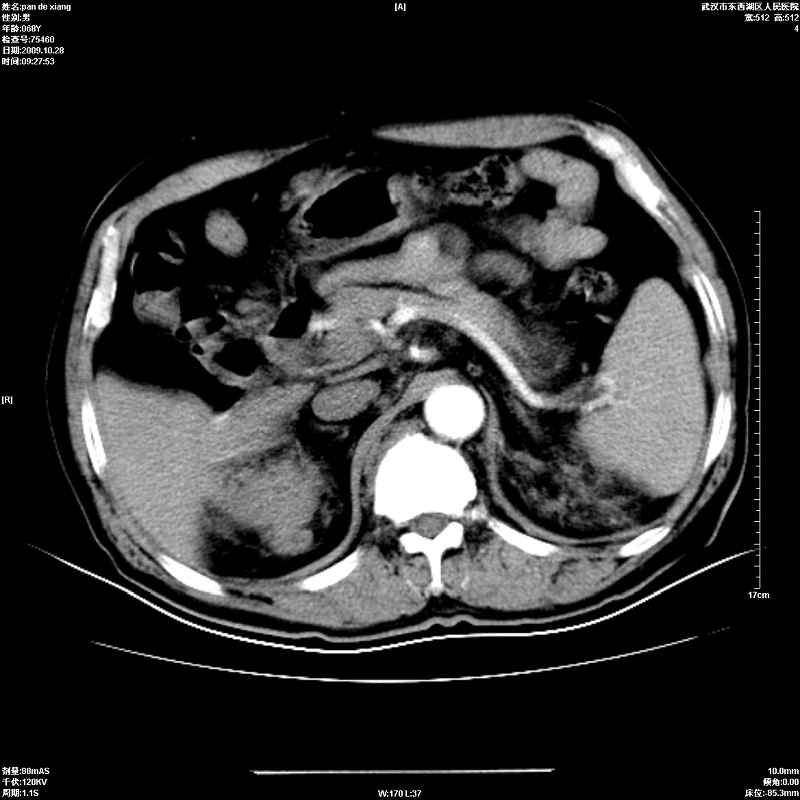

以下是引用杀毒软件在2009-10-28 20:41:00的发言:[br]结合临床考虑---白血病双肾改变或淋巴瘤。

以下是引用zxl51642在2009-10-29 9:59:00的发言:[br]结合临床“单克隆免疫球蛋白血症”,考虑双肾为继发损害并肾功能不全(尿中大量igg及少量iga、igm等大分子免疫球蛋白滤出所致继发损害),椎前软组织肿块为髓外造血。与浆细胞瘤有区别,平扫时有战友说的很清楚。